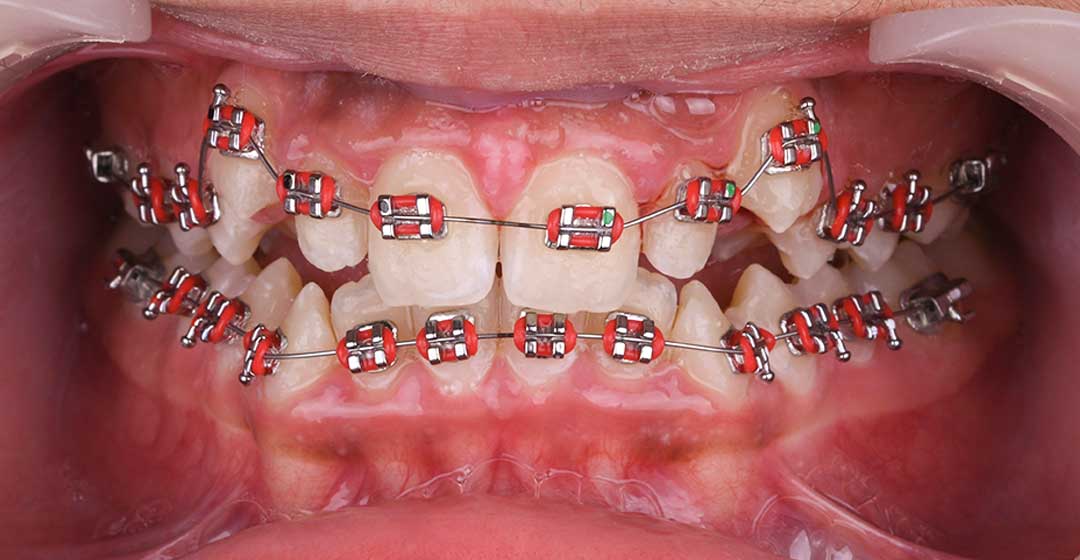

- Orthodontics